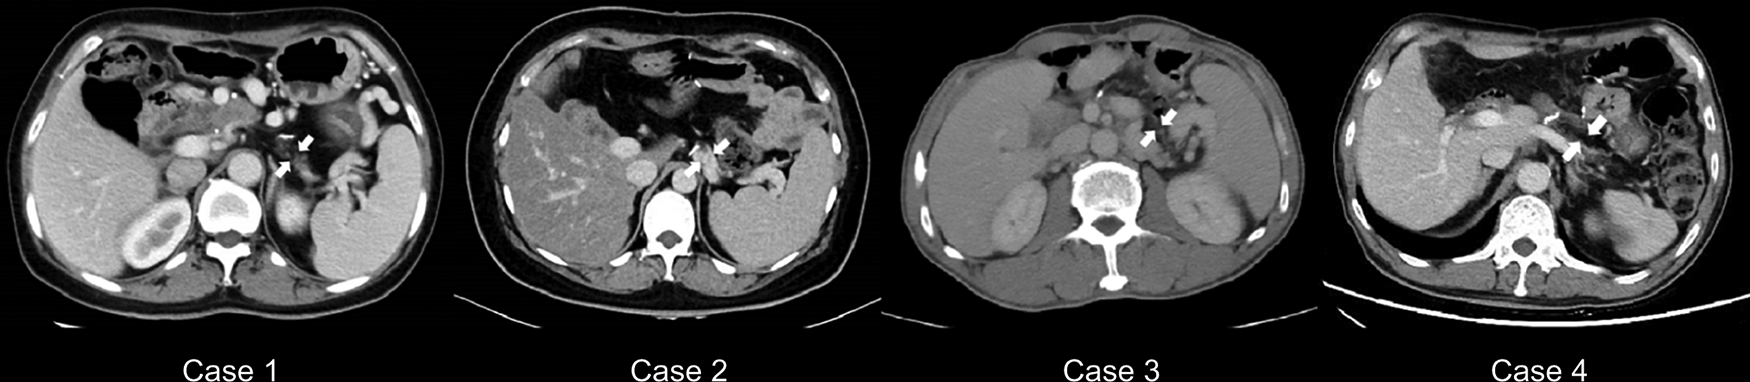

This study included two female and two male patients with atrophic glands and small ducts in the left pancreas who underwent PDO without pancreaticojejunostomy during PD. These patients (age range, 40–63 years) were diagnosed with a pancreatic head lesion with atrophy in the distal part preoperatively on an abdominal contrast-enhanced CT, and the width of their pancreatic body ranged from 7 to 9 mm (Table 1; Figure 1). The physical status of all patients was categorized as American Society of Anesthesiologists grade II. None of the patients had a history of DM, and preoperative FBG levels were between 5.39 and 5.99 mmol/L (Table 1). In addition, none of the patients complained of symptoms of exocrine pancreatic insufficiency, such as steatorrhea or oral pancreatic enzyme supplements before surgery.

Figure 1

Preoperative abdominal computed tomography scans. (A) The tumor or stone is marked in red. (B) The width of the pancreatic bodies is < 10 mm, with arrows highlighting the atrophy of the pancreatic bodies. (C) The thickness of the pancreatic bodies is < 10 mm in the image, with arrows indicating the atrophy of the pancreatic bodies.